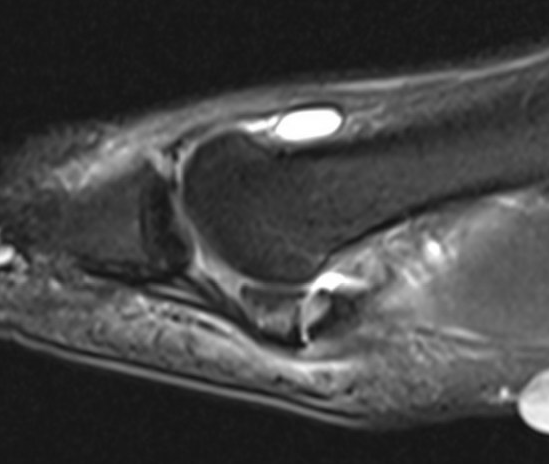

CT demonstrates irregular borders consistent with fracture of tibial sesamoid

Edema on T2 MRI indicates likely acute fracture